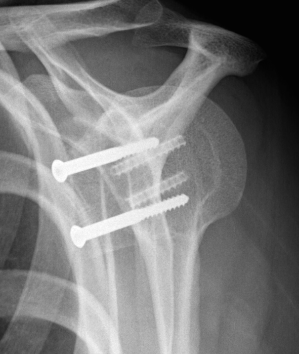

Case 2: Large glenoid defect